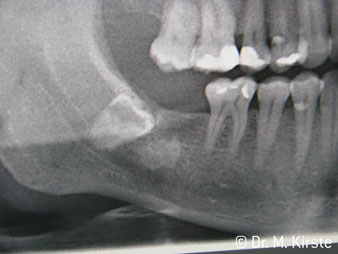

На Международной стоматологической выставке (IDS), состоявшейся в этом году в Кельне, фирма W&H обнародовала действительно мировую новинку: новый угловой наконечник с наклоном головки под 45° для челюстно-лицевой хирургии. Он не только сочетает в себе преимущества прямых и угловых хирургических наконечников, но одновременно позволяет значительно облегчить доступ к области лечения. Доступ к молярам стал значительно легче даже у пациентов с ограниченным открыванием рта.

Угол 45° наконечника был выбран специально с учетом широкого круга преимуществ. Коллеги, которые работают в хирургии, и для которых этот наконечник был изначально создан, быстро оценят возможность эффективно работать в очень стесненном пространстве. В частности, при удалении зуба мудрости (рис. 2) не нужно сильно раздвигать мягкие ткани в области щеки (рис. 3). Конструкция головки наконечника в сочетании с небольшим поворотом головки во время препарирования позволяет быстро и безопасно выполнять работу в области задних коренных зубов.

Профессиональная конструкция подшипников внутри головки обеспечивает тихую работу бора; впечатляет атравматичное разделение зуба и корня (рис. 4-9).